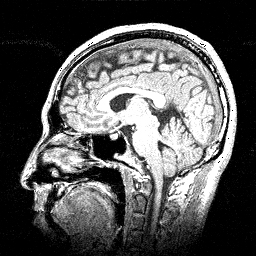

私の横顔

(1997年頃)

ちゃんと見て!